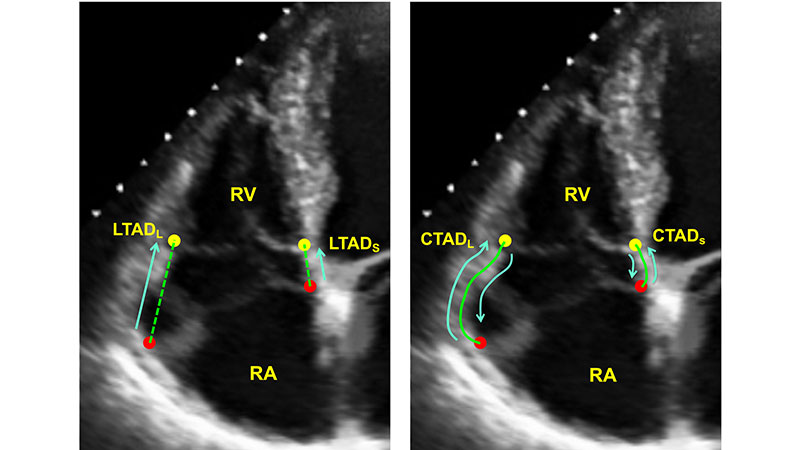

An initial validation of a deep learning system for right ventricle assessment using automated tracking of the tricuspid annulus; figure demonstrates representative lateral and septal annular displacement performed both manually and by machine learning algorithm.